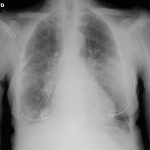

The appropriate position of radiology in COVID-19 diagnosis and treatment—current status and opinion from China

Progress and prospect on imaging diagnosis of COVID-19